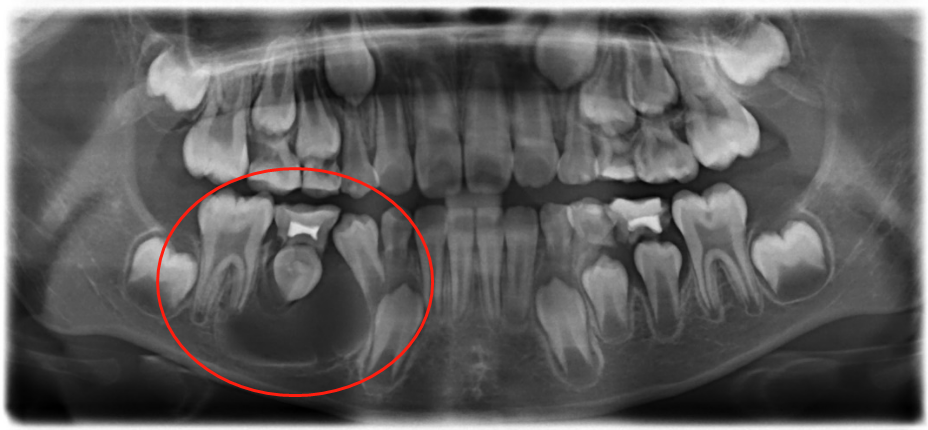

在X光片显示下,鹏鹏右下颌骨有大面积囊性阴影,而且松动的乳磨牙和未萌出的恒牙已经出现牙根外吸收的现象,如不给予治疗,囊肿有可能吸收掉整颗恒牙和部分颌骨骨质。

(术后四个月X光片)